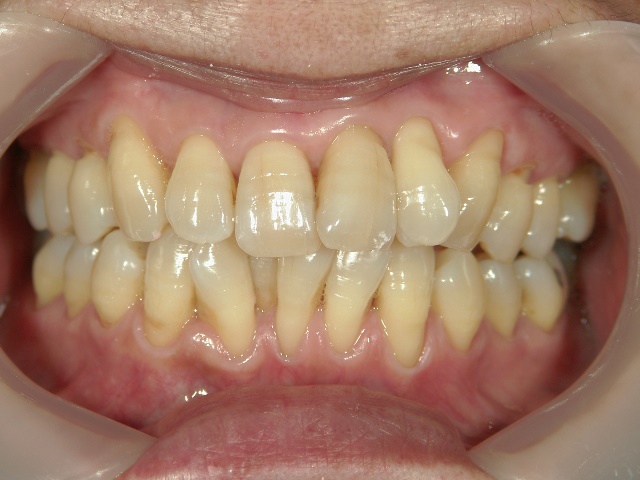

矯正歯科 治療前矯正歯科 治療前

矯正歯科 治療前